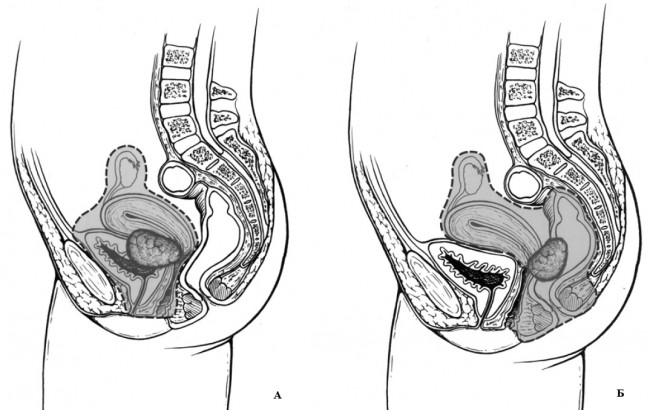

В представленном материале из 154 хирургических вмешательств, выполненных по поводу местно-распространенных опухолей органов малого таза 113 (73,4%) классифицированы как ЭМТ. Терминологически ЭМТ подразумевает полное моноблочное удаление всех органов малого таза. Первое сообщение о тазовой эвисцерации в лечении распространенных злокачественных опухолей было представлено A. Brunschwig в 1948 году [7]. Первым же исполнителем данной операции в 1940 году был E. Bricker. Но сообщили авторы о своем опыте лишь спустя 10 лет, в 1950 году [6]. В последующем многие специалисты сообщали о своем опыте выполнения ЭМТ при лечении распространенных злокачественных опухолей шейки и тела матки, влагалища, прямой и ободочной кишок, мочевого пузыря, предстательной железы и других органов. Некоторые специалисты, в том числе и автор первой публикации о подобном вмешательстве A. Brunschwig обозначал данное вмешательство как экзентерация органов малого таза [8]. Принимая во внимание, что эти два термина являются синонимами, с той лишь разницей, что корень у одного латинский, а у другого – греческий, то спор по поводу названия вмешательства нельзя рассматривать как принципиальный. Важно понимать, что ЭМТ подразделяются на передние, задние и полные, а также супра- и инфралеваторные (рис. 7).

Рис. 7. Объем удаляемых тканей при передней (А) и задней (Б) эвисцерации малого таза.

Эта классификация создана и впервые использована для гинекологических больных, чаще всего для обозначения комбинированных операций при раке шейки матки [12]. В дальнейшем данная терминология была перенесена в клиническую практику оперативного лечения всех опухолей малого таза.

Передняя эвисцерация (рис. 7А) включает в себя удаление мочевого пузыря, уретры, влагалища, матки с придатками, всех прилегающих тканей вплоть до стенки малого таза. Задняя эвисцерация (рис. 7Б) включает удаление матки с придатками, прямой кишки, и всех прилегающих тканей до стенки малого таза. Полная (тотальная) эвисцерация предполагает моноболочное удаление всех органов малого таза. При этом, в зависимости от отношения нижней границы резекции органов к диафрагме таза применяются термины супралеваторной и инфралеваторной эвисцерации малого таза.